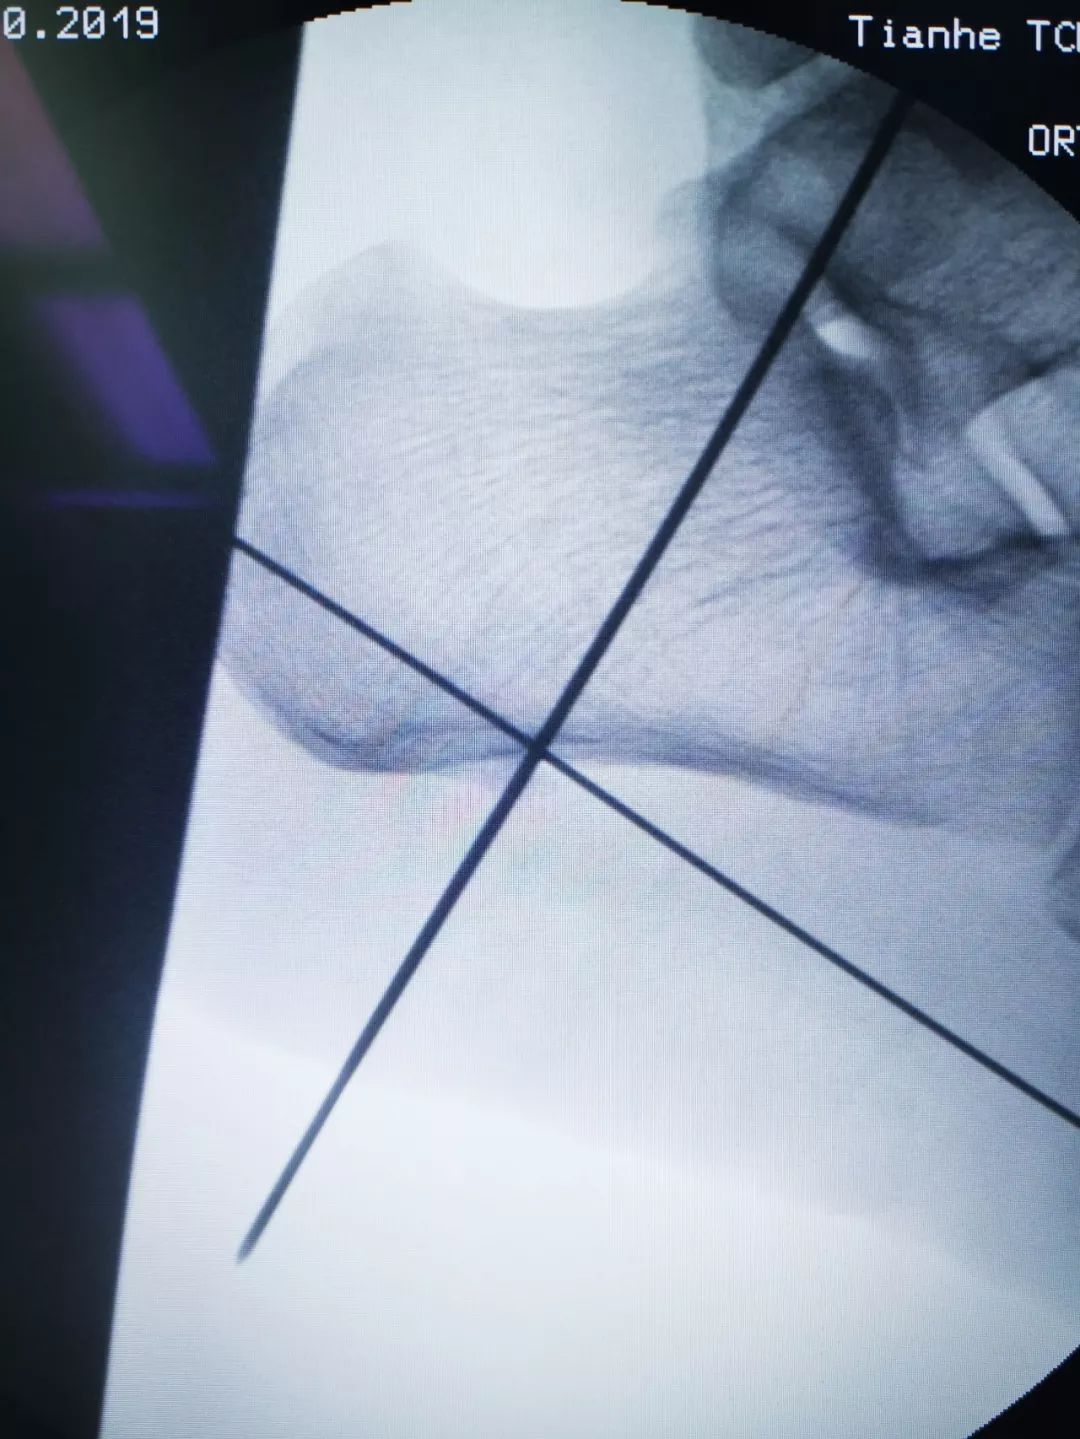

患者骆某 82岁,“反复左足跟疼痛走路困难4年”入院,经X线检查诊断为“左侧跟骨骨刺”。此前患者曾尝试各种治疗方法效果均不理想。

术前检查

骨伤二科主任医师方磊经过与治疗团队认真讨论后,为患者制定了全新的微创手术方案,行关节镜下跟骨骨刺摘除术,手术取足跟部内侧两个0.5cm长小切口,在关节镜监视下切除增生骨赘,清理修整骨刺周围炎性组织,同时行跖筋膜松解,成功完成手术,目前患者术后恢复良好。